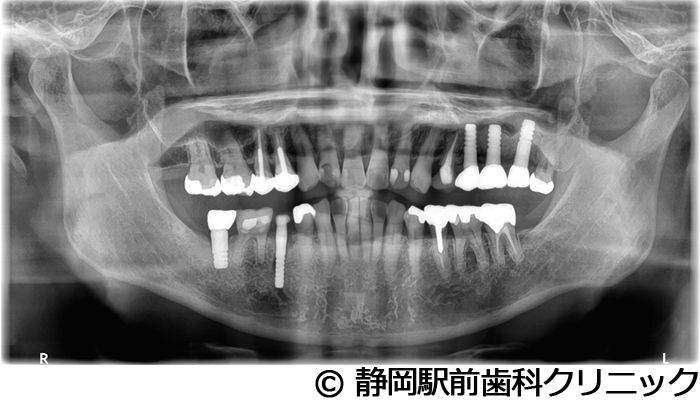

【症例4】全顎的インプラントとセラミックによる審美補綴

- 治療前

- 治療後

- 治療名

- 全顎的インプラントとセラミックによる審美補綴

- 費用

- 1,200,000円(税込)

- 期間

- 1年3ヵ月

治療内容

患者様の症状

左上ブリッジが歯根破折してしまい、他院で入れ歯を作ったが使い心地がよくないため、インプラント治療希望。

治療方法

抜歯後、骨治癒後にCTを撮影して、綿密に治療計画を立てた。上顎洞の距離やインプラント同士のバランスを熟慮し、インプラントを埋入した。全体的な噛み合わせの調整を重ねた後、人工歯を被せて咬合と見た目の回復を行った。

治療結果

入れ歯のような違和感が全くなく、力を入れてしっかり噛むことができるので、食事することが楽しくなったとご満足いただけました。見た目もセラミックの歯が入ったので、自分の歯が戻ったようだと喜んでいただきました。

※治療結果は個人差があります。

治療を行う上での注意点(リスク・副作用)

術後は、出血、腫れ、痛みなどが出る可能性があります。